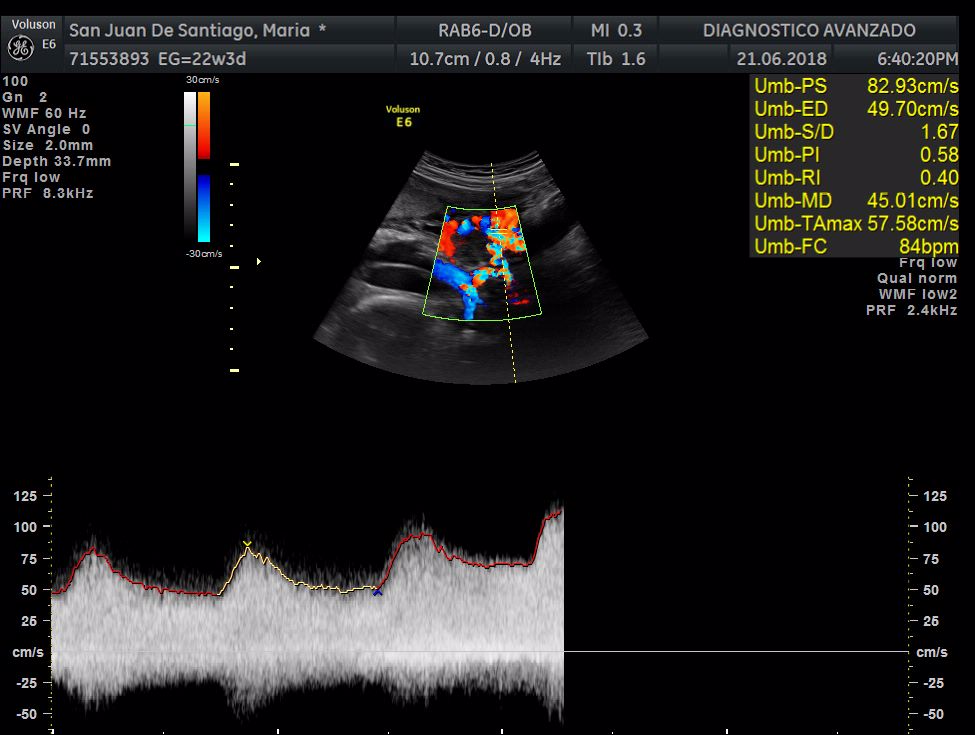

¡Hola a todos! Hoy hemos ido a hacer la tradicional ecografía 3D de la niña, os dejamos todo el material (aunque es un poco demasiado).